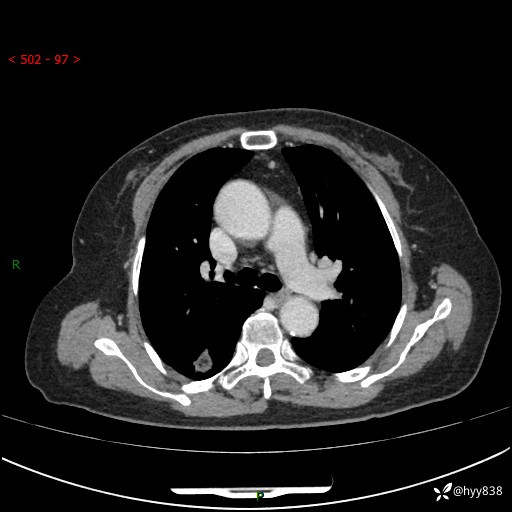

71岁/女,发现肺结节1月。偶然发现孤立肺结节,邻近叶间裂凹陷---结果公布(再回首)

【患者信息】:71岁/女

【主诉】:发现肺结节1月

【现病史及既往史】:2024年9月患者因“胆囊结石”于我院肝胆外科住院,期间完善胸部CT提示:右下肺结节灶,高危结节?感染?,病程中无畏寒发热,无咳嗽、咳痰,无活动后气短,无心慌胸闷,无胸痛、咯血,无头晕头痛,无腹痛腹泻,无四肢肌肉酸痛等不适,当时建议其择期复查。今日患者为求进一步复查就诊于我院,完善胸部CT提示:右肺结节,较前一致,遂门诊“肺部结节”收入我科。 自本次起病以来,患者精神、饮食、睡眠可,大小便正常,体力、体重未见明显异常。

【检查】:胸部CT平扫+增强